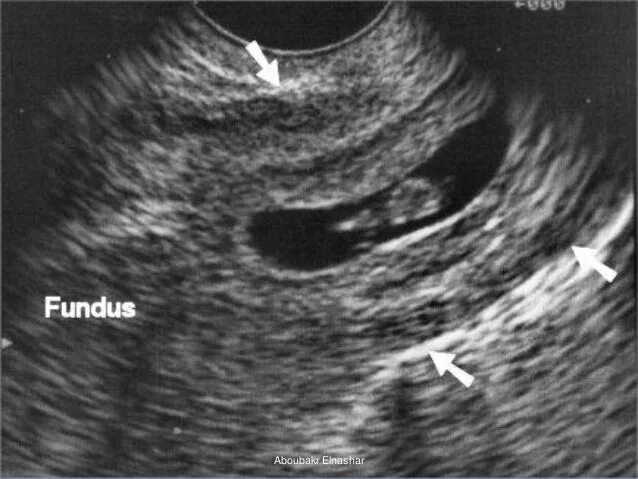

Можно ли на узи увидеть внематочную беременность